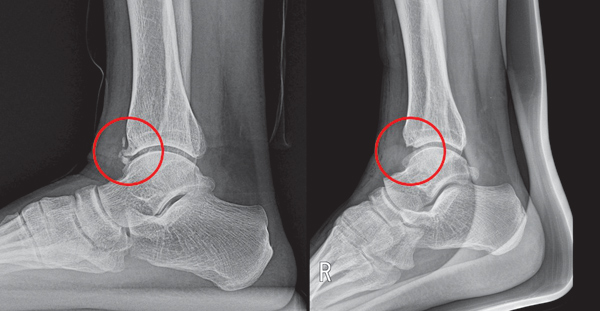

하지만 평소 발목이 시리고, 저리고, 욱신거리는 다양한 증상에 시달리고 있다면 발목염좌 후유증의 하나일 수 있다. 불필요한 뼈가 자라 발목 손상을 유발하는 골성 전방충돌 증후군(anterior impingement syndrome)을 의심해야 한다.

그렇다면 왜 발목염좌로 인해 불필요한 뼈가 자라는 것일까? 염좌는 발목인대 파열 뿐만 아니라 발목연골 내측 경계부에 손상을 유발한다. 관절연골과 막에 직접적인 미세손상을 가하게 되면서 비정상적인 조직재생을 유도, 결국 불필요한 뼈인 골극(Spur)이 형성될 수 있다. 그래서 파열된 인대뿐 아니라 체계적인 족부 재활을 통해 주변조직, 구조물의 회복을 도모해야 한다.

불필요한 뼈가 자라 발목 손상을 유발하는 골성 전방충돌 증후군 환자의 엑스레이 사진.